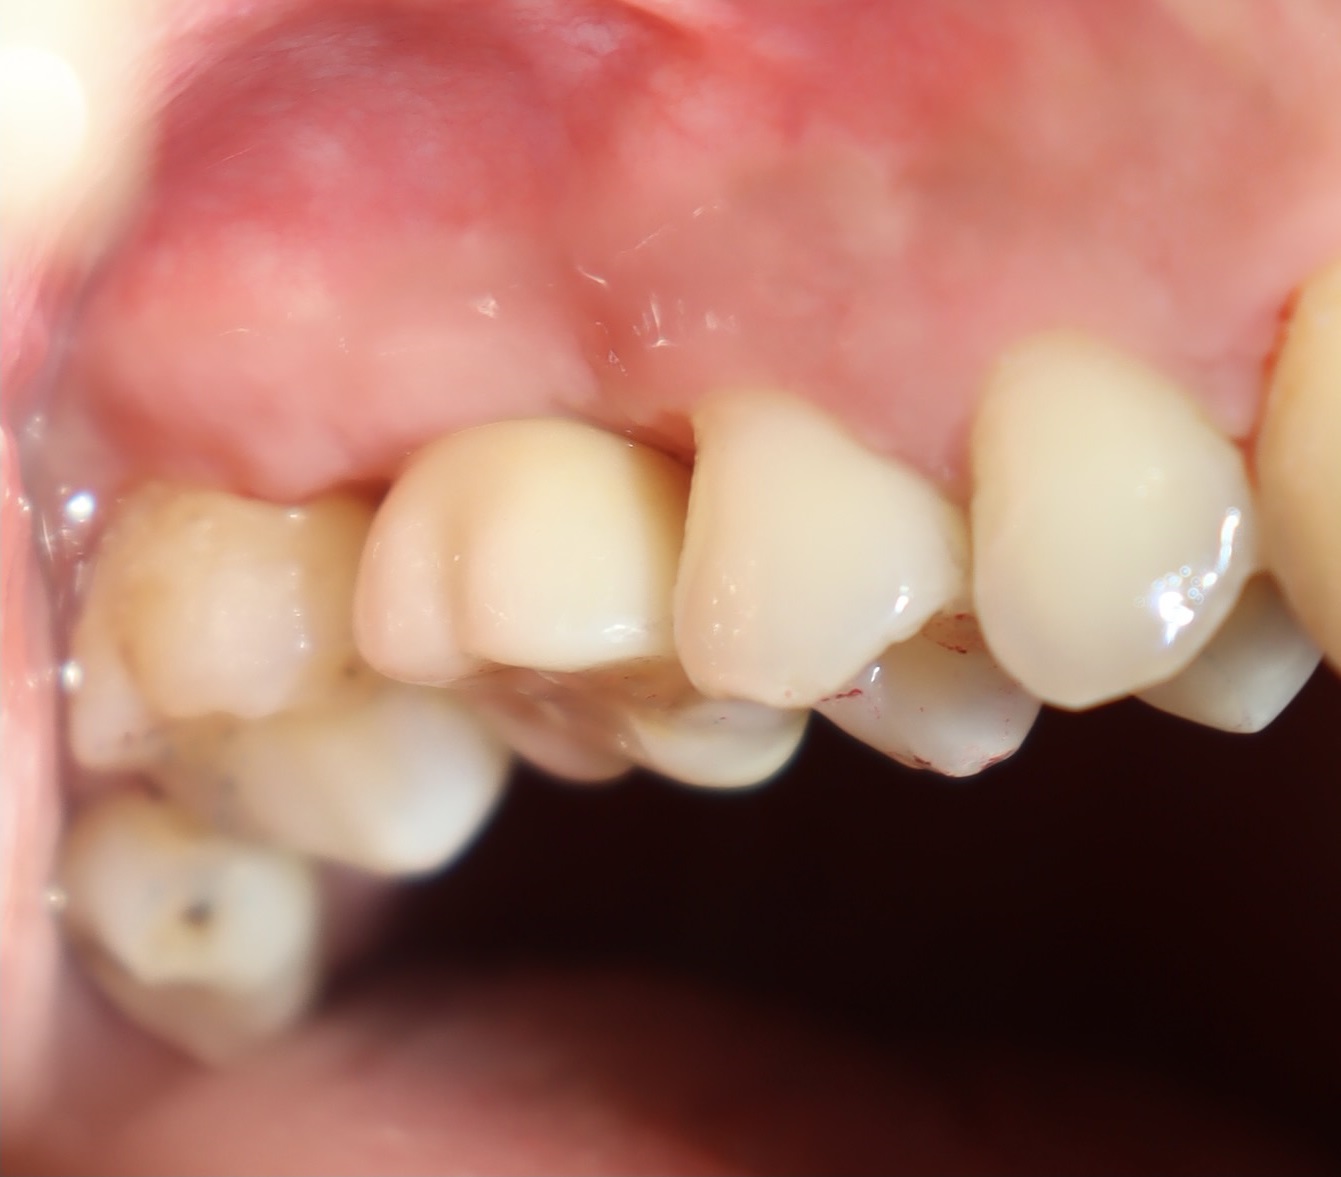

術後照片